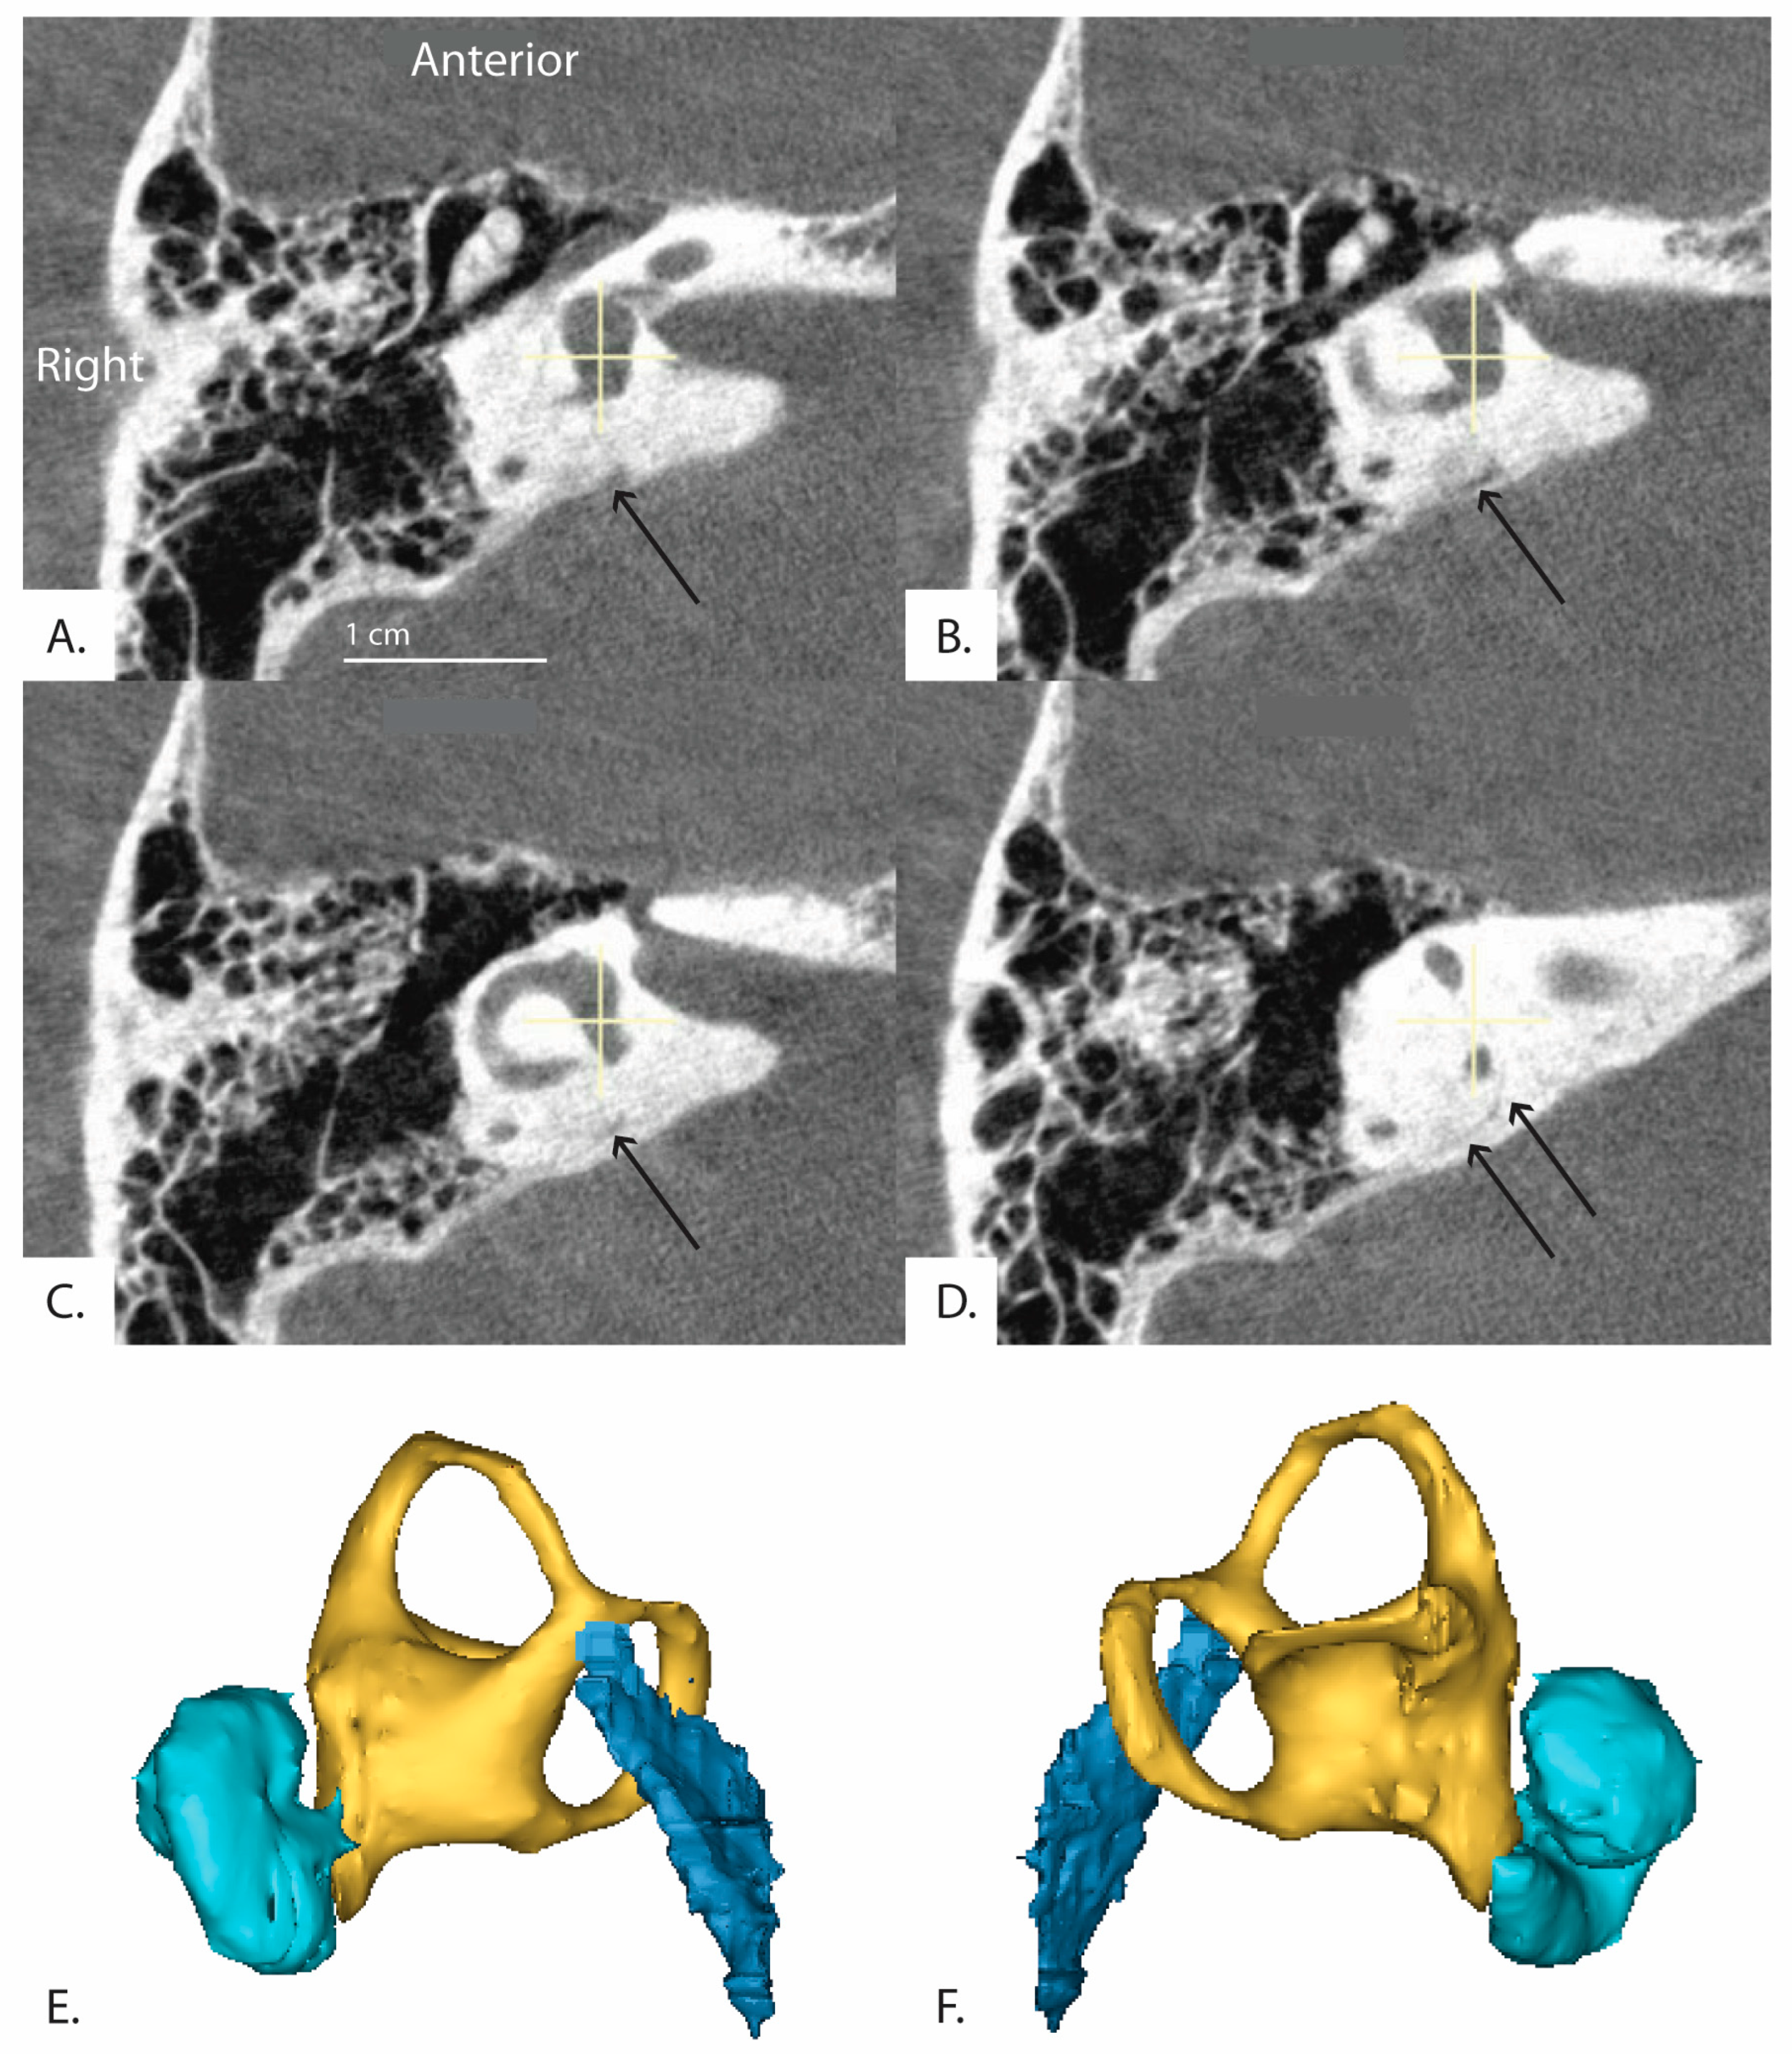

Figure 4.

Example demonstrating variability in the determined angle depending on application of the tool. Bächinger et al. software used to measure angles in the same image. (A) = 114.64° and (B) = 132.47°. Depending on the settings of the software, different angles for the same image can result.

These results may be due to limitations inherent to the software and use of a 2D image. Because the software involves manual and subjective adjustment to the predefined shapes and lines (Figure 1) used to measure the of the vestibular aqueduct, there was variability of results depending on how the user manually fit the shapes and lines to the image. This is supported by our finding of moderate reliability in the measurements when the software is used by three different raters to evaluate a randomly selected subset of our sample. As presented in Figure 4, slight variations in how the user fit the predefined horizontal semicircular canal and vestibule shape (purple, Figure 4) to the same image resulted in an that either fell below 120 degrees at 114.64 degrees and therefore in the category of normal adults or patients with degenerative Meniere’s pathology, or above 120 degrees at 132.47 degrees. This example would not be categorized as hypoplastic Meniere’s disease with > 140; however, the variability places the patient outside of the established range for normal patients ( < 120). The algorithm could be further standardized with added constraints to improve the reliability of the measurements.